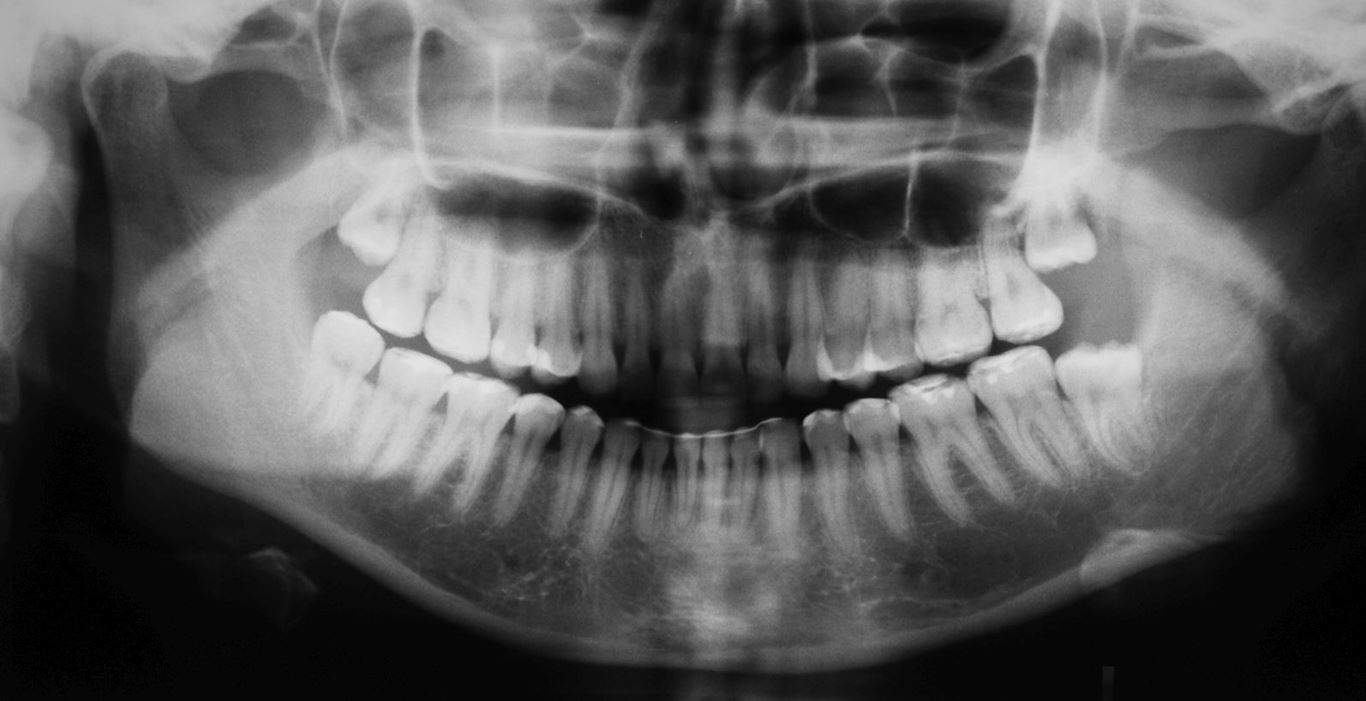

Wykonano także modele diagnostyczne zaartykulowane w relacji centralnej (RC), którą zarejestrowano ze względu na zwiększone napięcie mięśniowe z wykorzystaniem deprogramatora Koisa (ryc. 13-15), oraz zdjęcie pantomograficzne (ryc. 16) i cefalometryczne. Analiza modeli w RC wykazała przesunięcie żuchwy w kierunku doprzednim w stosunku do pozycji maksymalnego zaguzkowania i przedwczesne kontakty funkcjonalne na zębach bocznych, co tłumaczyło obecność odprysków szkliwa na brzegach siecznych górnych zębów (szczególnie wyraźne na zębie 12) (ryc. 14, 17). Na modelach wykonano studium funkcjonalne mające na celu określenie, w jaki sposób można odtworzyć prawidłową funkcję, tzn. uzyskać prawidłowy nagryz pionowy i poziomy oraz prowadzenie przednie (ryc. 18-20).

Minimalne zachodzenie pionowe, a w pozycji RC ustawienie zębów przednich w zgryzie tête à tête nasuwały podejrzenie wady gnatycznej. Analiza zdjęcia cefalometrycznego wykazała wprawdzie prognatyczny typ twarzy, jednak I klasę szkieletową, rotację i translację żuchwy w normie oraz neutralną relację sagitalną i wertykalną podstaw (ryc. 21). Pozwoliło to zaplanować poprawę relacji pomiędzy górnym i dolnym łukiem zębowym przez leczenie ortodontyczne poprzedzone ekstrakcją jednego dolnego zęba siecznego oraz dolnych zębów ósmych. Po leczeniu ortodontycznym zaplanowano chirurgiczne wydłużenie koron przednich zębów górnych i wykonanie adhezyjnych rekonstrukcji ceramicznych na wszystkich zębach szczęki i żuchwy z wyłączeniem drugich zębów trzonowych.

Drugie zęby trzonowe nie zostały włączone w rekonstrukcję pomimo znacznej utraty wysokości koron. Dzięki temu podniesienie wysokości zwarcia mogło być zminimalizowane oraz uniknięto konieczności preparacji zniszczonych powierzchni zwarciowych tych zębów. Po przebudowie warunków zwarciowych na pozostałych zębach uzyskano prowadzenie przednie i kłowe, co potencjalnie dało ochronę zębów trzonowych przed destrukcyjnymi siłami bocznymi.